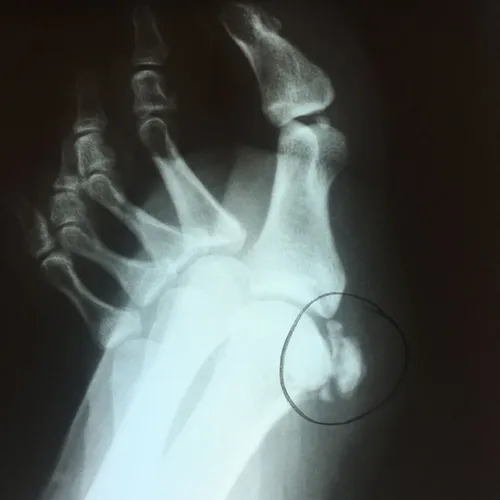

Patient had chronic pain after comminuted sesamoid fracture. After conservative care, patient had total sesamoidectomy and is pain free 3 months postop

Pre and Postop Tibial Sesamoidectomy